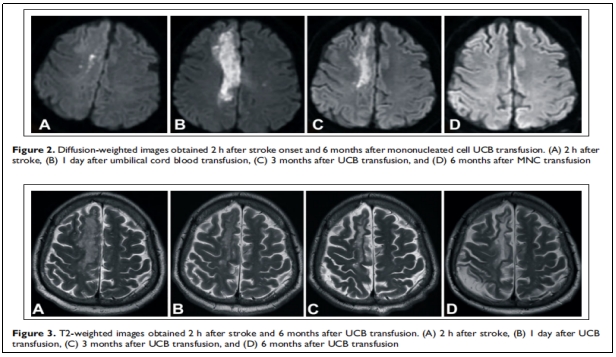

案例研究 | 6名急性中风患者接受细胞治疗后,运动功能完全恢复

近期,Tian-Kuo Lee等人在《Sage Journals》发表了一项关于急性中风的I期临床试验,据文献显示,该研究采用脐带血(UCB)单核细胞(MNCs)治疗急性中风患者,结果显示,患者各项评估指标基本恢复正常水平。